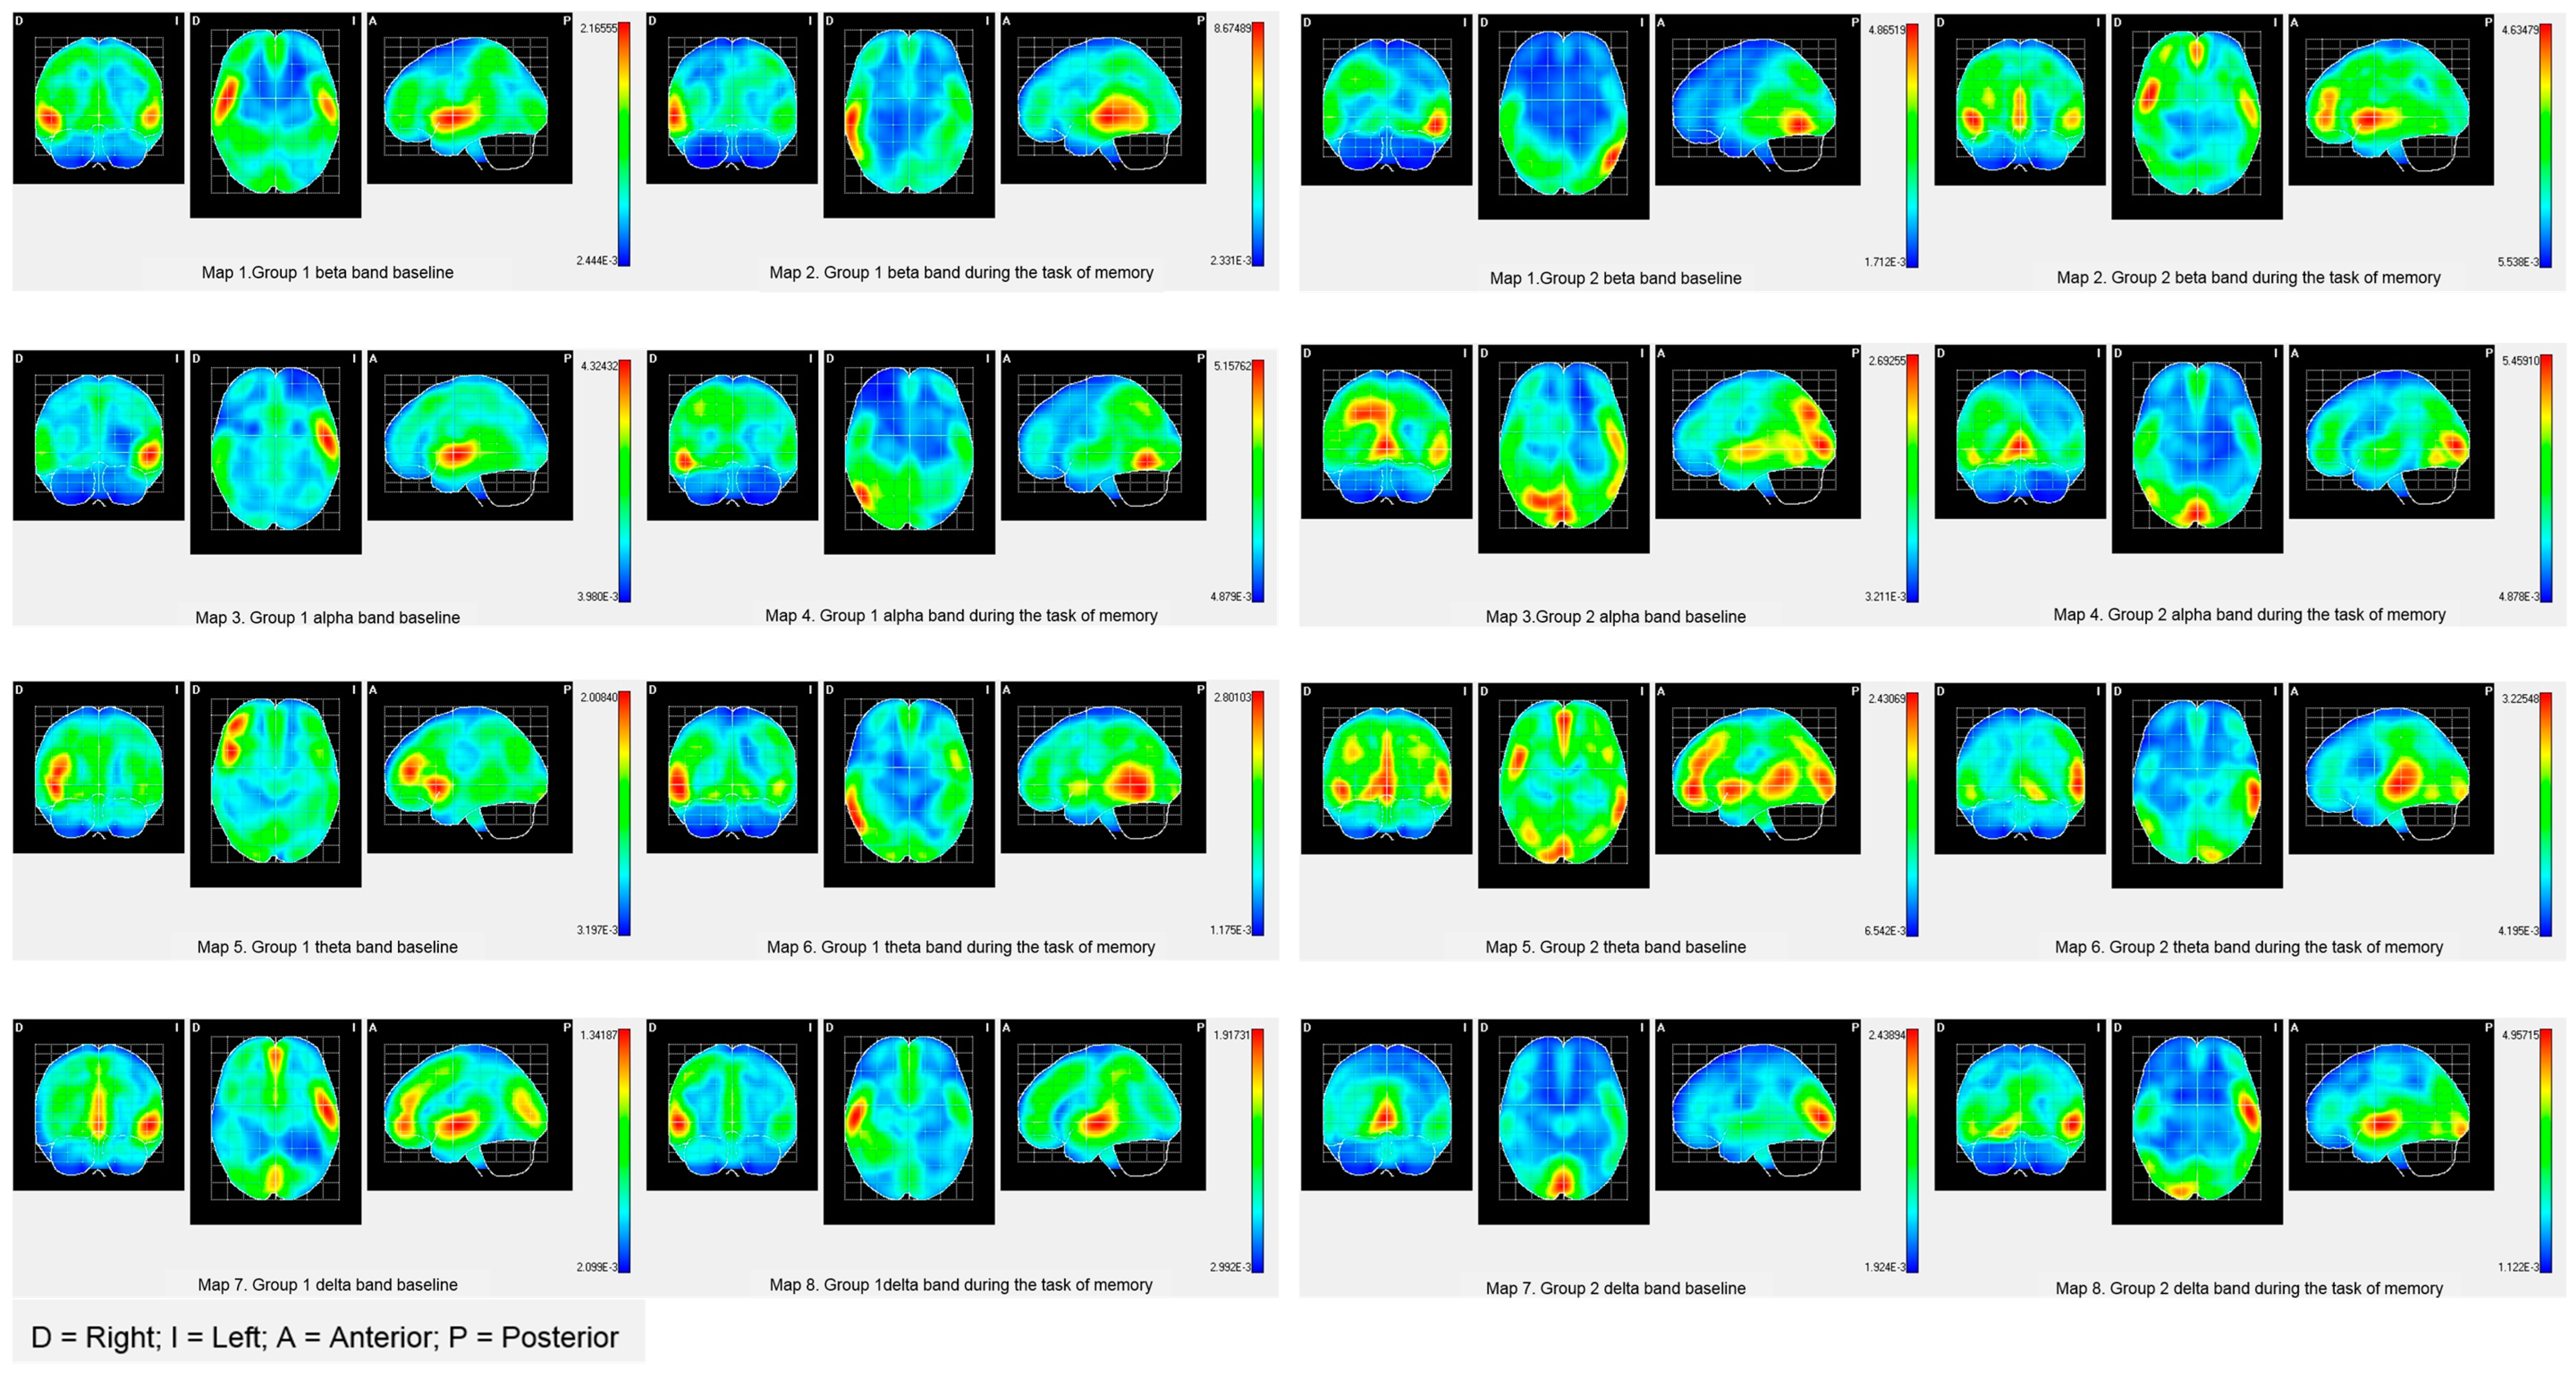

| Brain Activities | PALA | BA | X | Y | Z | T2 Hotelling | Mean | |

|---|---|---|---|---|---|---|---|---|

| G1 | G2 | |||||||

| Beta band | ||||||||

| Baseline | Left Angular gyrus | 39 | 140 | 104 | 144 | 9.1357 ** | 0.3452 | 0.3662 |

| Task of memory | Right superior Parietal Lobe | 7 | 76 | 126 | 164 | 11.0486 * | 0.0688 | 0.2250 |

| Alpha band | ||||||||

| Baseline | Right Cingulate Region | 7 | 76 | 100 | 136 | 22.0856 *** | 0.1019 | 0.1119 |

| Task of memory | Postcentral area right | 3 | 76 | 148 | 128 | 11.3437 * | 0.2848 | 07802 |

| Theta band | ||||||||

| Baseline | Superior left occipital area | 19 | 120 | 96 | 184 | 15.6583 ** | 0.1442 | 0.4200 |

| Task of memory | Left Occipital Pole | 18 | 108 | 52 | 192 | 9.6772 * | 0.4046 | 0.4883 |

| Occipitotemporal area Lateral left | 18 | 108 | 56 | 168 | 9.1443 * | 0.7235 | 0.7850 | |

| Lingual Area Left | 18 | 108 | 60 | 180 | 9.39411 * | 20.845 | 25.436 | |

| Delta band | ||||||||

| Baseline | Right Lateral Orbitofrontal Region | 11 | 72 | 48 | 76 | 11.37077 * | 0.0926 | 0.1901 |

| Task of memory | Right parahipocampal area | 30 | 64 | 52 | 116 | 18.3420 ** | 0.4071 | 0.4257 |

| Right lateral Occipitotemporal area | 30 | 64 | 52 | 120 | 18.5904 ** | 0.3481 | 0.3735 | |

| Hippocampal area right | 30 | 64 | 52 | 112 | 17.9080 ** | 0.4427 | 0.4594 | |